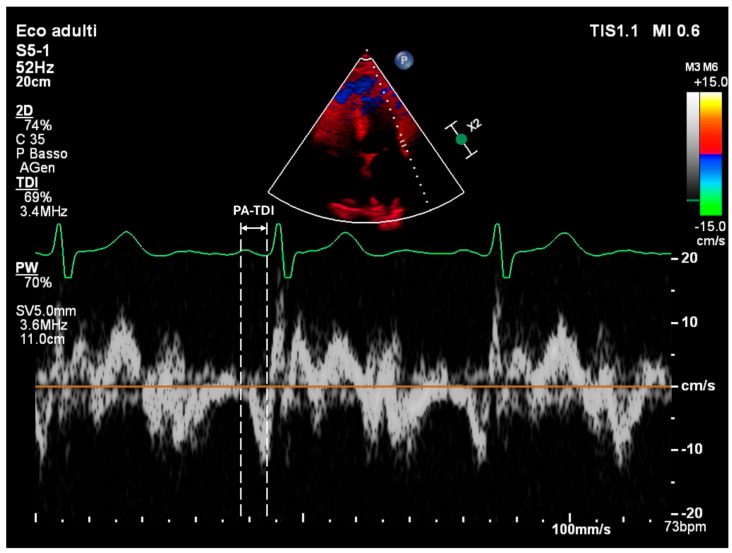

背景:阵发性心房颤动(PAF)是一种常见的心律失常,常采用导管消融治疗,尤其是肺静脉隔离(PVI)。然而,复发仍然很频繁,并且通常与未被识别的左心房结构和功能重塑有关。方法:我们引入超声心动图心房应变和传导评估(EASE)评分作为一种理论的、无创的模型,对导管消融治疗PAF患者的复发风险进行分层。该评分基于综合超声心动图参数能够反映与消融结果相关的心房重构程度的假设。结果:EASE评分结合了六项超声心动图指标——左心房储层应变(LASr)、心房传导时间(PA-TDI)、左心房容积指数(LAVI)、刚度指数(E/ E′/LASr)、E/ E′比和收缩应变(LASct)——每项指标都代表了结构、电或机械重构。总分从0到12分,将患者分为心律失常复发的低、中、高风险三类。初步回顾性数据显示,较高的EASE评分与消融后复发率增加之间存在显著关联。结论:EASE评分为PAF消融的无创风险预测提供了生物学上合理的多维框架。有必要进行前瞻性研究以验证其临床应用并完善其结构。

Background: Paroxysmal atrial fibrillation (PAF) is a common arrhythmia often treated with catheter ablation, particularly pulmonary vein isolation (PVI). However, recurrence remains frequent and is often linked to unrecognized structural and functional remodeling of the left atrium. Methods: We introduce the Echocardiographic Atrial Strain and conduction Evaluation (EASE) score as a theoretical, noninvasive model to stratify recurrence risk in patients undergoing catheter ablation for PAF. The score is based on the hypothesis that integrated echocardiographic parameters can reflect the extent of atrial remodeling relevant to ablation outcomes. Results: The EASE score combines six echocardiographic metrics-left atrial reservoir strain (LASr), atrial conduction time (PA-TDI), left atrial volume index (LAVI), stiffness index (E/e'/LASr), E/e' ratio, and contractile strain (LASct)-each representing structural, electrical, or mechanical remodeling. The total score ranges from 0 to 12, stratifying patients into low, intermediate, and high-risk categories for arrhythmia recurrence. Preliminary retrospective data suggest a significant association between higher EASE scores and increased recurrence rates following ablation. Conclusions: The EASE score offers a biologically plausible, multidimensional framework for noninvasive risk prediction in PAF ablation. Prospective studies are warranted to validate its clinical utility and refine its structure.